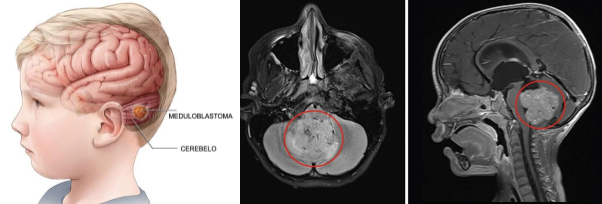

- Meduloblastoma

- Prevalência: o tumor maligno mais comum em crianças, frequentemente localizado no cerebelo.

- Características: pode se disseminar pelo líquido cefalorraquidiano, alcançando outras áreas do cérebro e medula espinhal.

- Tratamento: cirurgia seguida de radioterapia e quimioterapia; em crianças, o enfoque é em minimizar danos neurológicos.